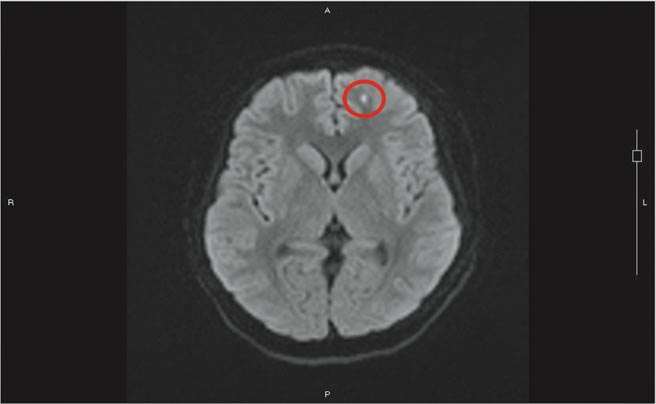

17岁阿成因车祸造成大、小腿开放性骨折,住院时性格丕变,原本只是青春期叛逆却变成恶霸,白天睡觉晚上吵闹,对家人医护及看护善意叮嘱都不屑,甚至顶撞。医生发现他反应迟缓、意识怪异,且经检查大脑未有损伤,也排除酒驾与药物滥用,高度怀疑是骨折併发脂肪脑栓塞。

骨头中有脂肪丰富的骨髓,当病患骨折时,脂肪粒从断骨处释放散出,随着血液回流后先经过肺臟,因此脂肪栓塞常发生在肺部,但少年完全没有肺部症状。

神经内科医师黄炳钟推测病患可能因年轻,脂肪粒微小,通过肺部后再随血液至脑部而沉积在左边额叶及右边颞叶,这两处与情绪有关,才出现失序情形。

严可伦表示,病患经治疗后,脂肪粒逐渐由身体吸收,情绪恢復稳定,没有留下不可逆后遗症。骨折併发脂肪栓塞好发年轻人身上,因年轻人骨头内油脂含量丰沛,而全身骨骼中又以大、小腿骨等长骨油脂含量最丰富。